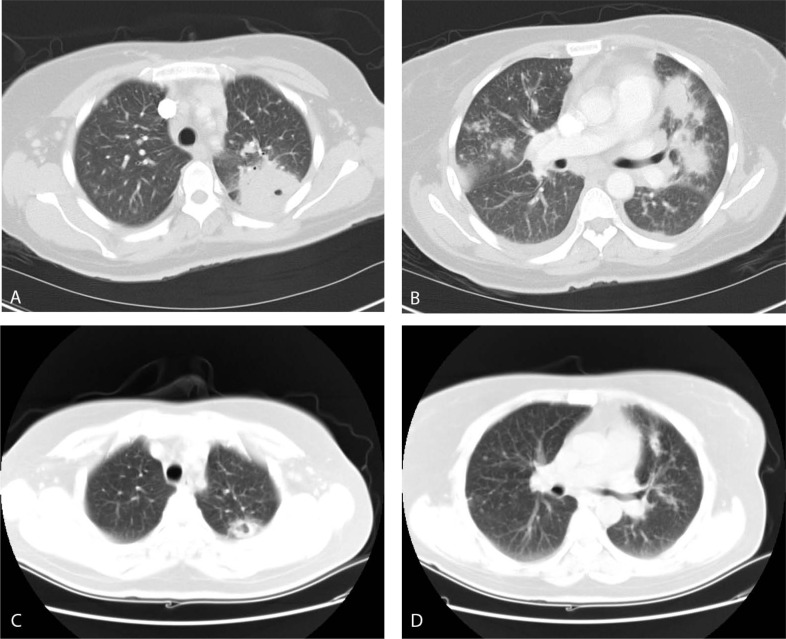

人类免疫缺陷病毒(HIV)相关的机会性感染(OI),包括吉氏肺囊虫肺炎(PCP),在抗逆转录病毒治疗(ART)下已经变得不那么常见了。尽管如此,OI仍然很常见,重要的是要对它们的存在保持警惕,并意识到ART和OI化学预防如何可能导致非典型疾病的表现。我们报告一例51岁的女性,HIV和CD4+ T辅助淋巴细胞计数> 200细胞/ul,抗逆转录病毒治疗和甲氧苄氨嘧啶/磺胺甲恶唑预防,表现为肺空洞性肿块,纵隔淋巴结病和胸腔积液。支气管肺泡灌洗(BAL)和经支气管活检(TBBx)阴性提示第二次诊断程序:经胸核心穿刺活检;最终诊断为肉芽肿性PCP。本病例表现为非常罕见的PCP,影像学上表现为肺大空化肿块,病理上表现为肉芽肿反应,同时由于BAL阴性和TBBx阴性,可能漏诊,需要经胸核心穿刺活检才能最终诊断。

Human Immunodeficiency Virus (HIV)-related Opportunistic Infections (OI), including Pneumocystis jiroveci pneumonia (PCP), have become much less commonplace with anti-retroviral therapy (ART). Despite this, OIs are still common and it is important to remain vigilant for their presence and be aware of how ART and OI chemoprophylaxis may lead to atypical disease presentations. We present the case of a 51-year-old woman with HIV and CD4+ T helper lymphocytes cell count > 200 cells/ul on both ART and trimethoprim/sulfamethoxazole prophylaxis who presented with cavitating lung masses, mediastinal lymphadenopathy and pleural effusions. Negative bronchoalveolar lavage (BAL) and transbronchial biopsy (TBBx) prompted a second diagnostic procedure with a transthoracic core needle biopsy; the final diagnosis was granulomatous PCP. This case showcases a very rare presentation of PCP, with both large cavitating lung masses on imaging and granulomatous reaction on pathology, as well as the challenge of a potentially missed diagnosis with negative BAL and TBBx requiring transthoracic core needle biopsy for a final diagnosis.